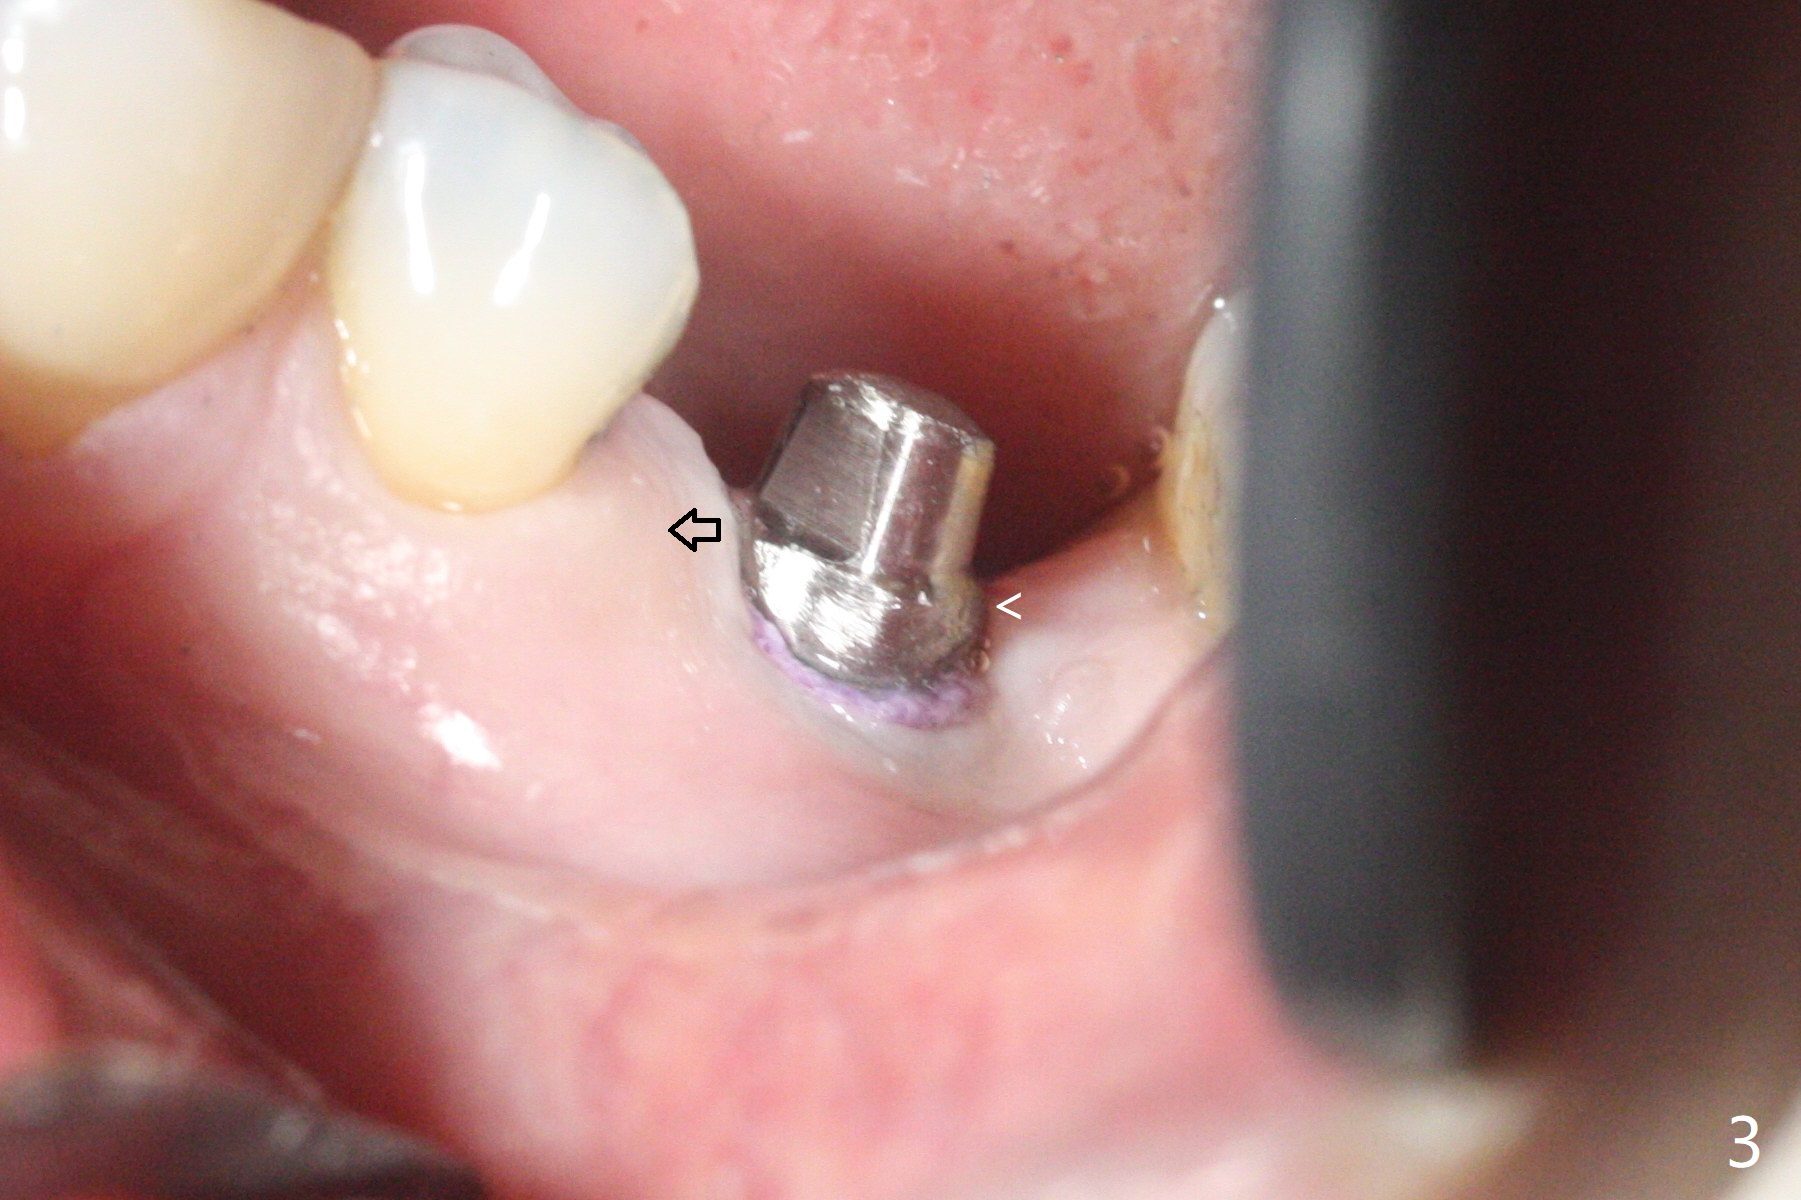

适当更改导板(为两段式接近圆柱状植体设计)钻洞顺序(根尖钻头小,而一段式植体根尖特别尖),5x14毫米一段式软组织水平植体植入,扭力大约35Ncm(图一),略微种深(图二:长箭头)后,磨短基台(与图一对比;左上6伸长),颊侧,远中,舌侧边缘降低(图二,三:<;增加基台高度,提高牙冠固位),制作临时牙冠(图四:P),主要目的将近中牙龈推向近中(图三:空箭头),暴露近中基台边缘,以后好取模。总之,一段式植体需要考虑临时修复。术后两个月临时牙冠和周围牙龈正常(图五)。术后4.5月轻度骨质吸收(图六),临床上看不出来螺纹将要暴露,取模。病人抱怨用临时牙冠咀嚼疼痛,不咬后没有不舒服,其实临时牙冠咬合面穿孔,牙龈正常,永久粘固剂没有外溢(图七)。术后4.5-6个月植体周围骨质吸收(图六,七)。牙槽嵴处钻洞应与植体直径一样才能减少骨质吸收。